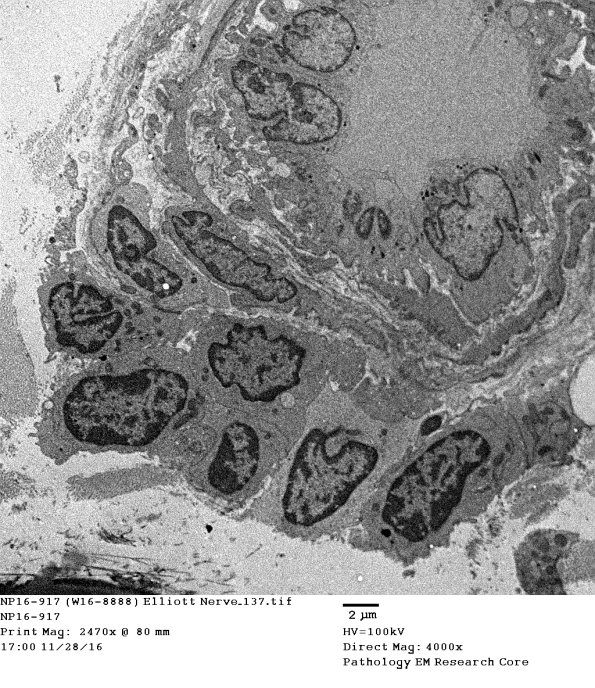

Endoneurial lymphocytes and rare plasmacytoid elements are also demonstrated ultrastructurally. (electron micrographs)